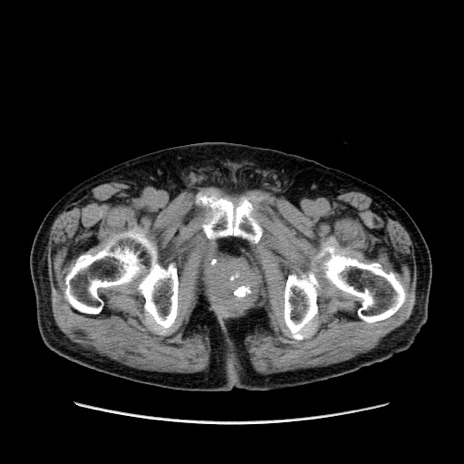

症例24(横断像)

【症例】80歳代男性

【主訴】左側腹部痛、嘔吐

【現病歴】本日早朝より左腹部に痛みあり。昼頃嘔吐認めたため、救急要請。

【既往歴】直腸癌(Mile手術)、胆摘

【身体所見】意識清明、BT 35.9℃、BP 221/93mmHg、SpO2 97%(RA) 、腹部:左ストーマ周囲に限局性の腹部膨隆あり。 膨隆部自発痛・圧痛あり・軟。

【データ】WBC 7700、CRP 0.09